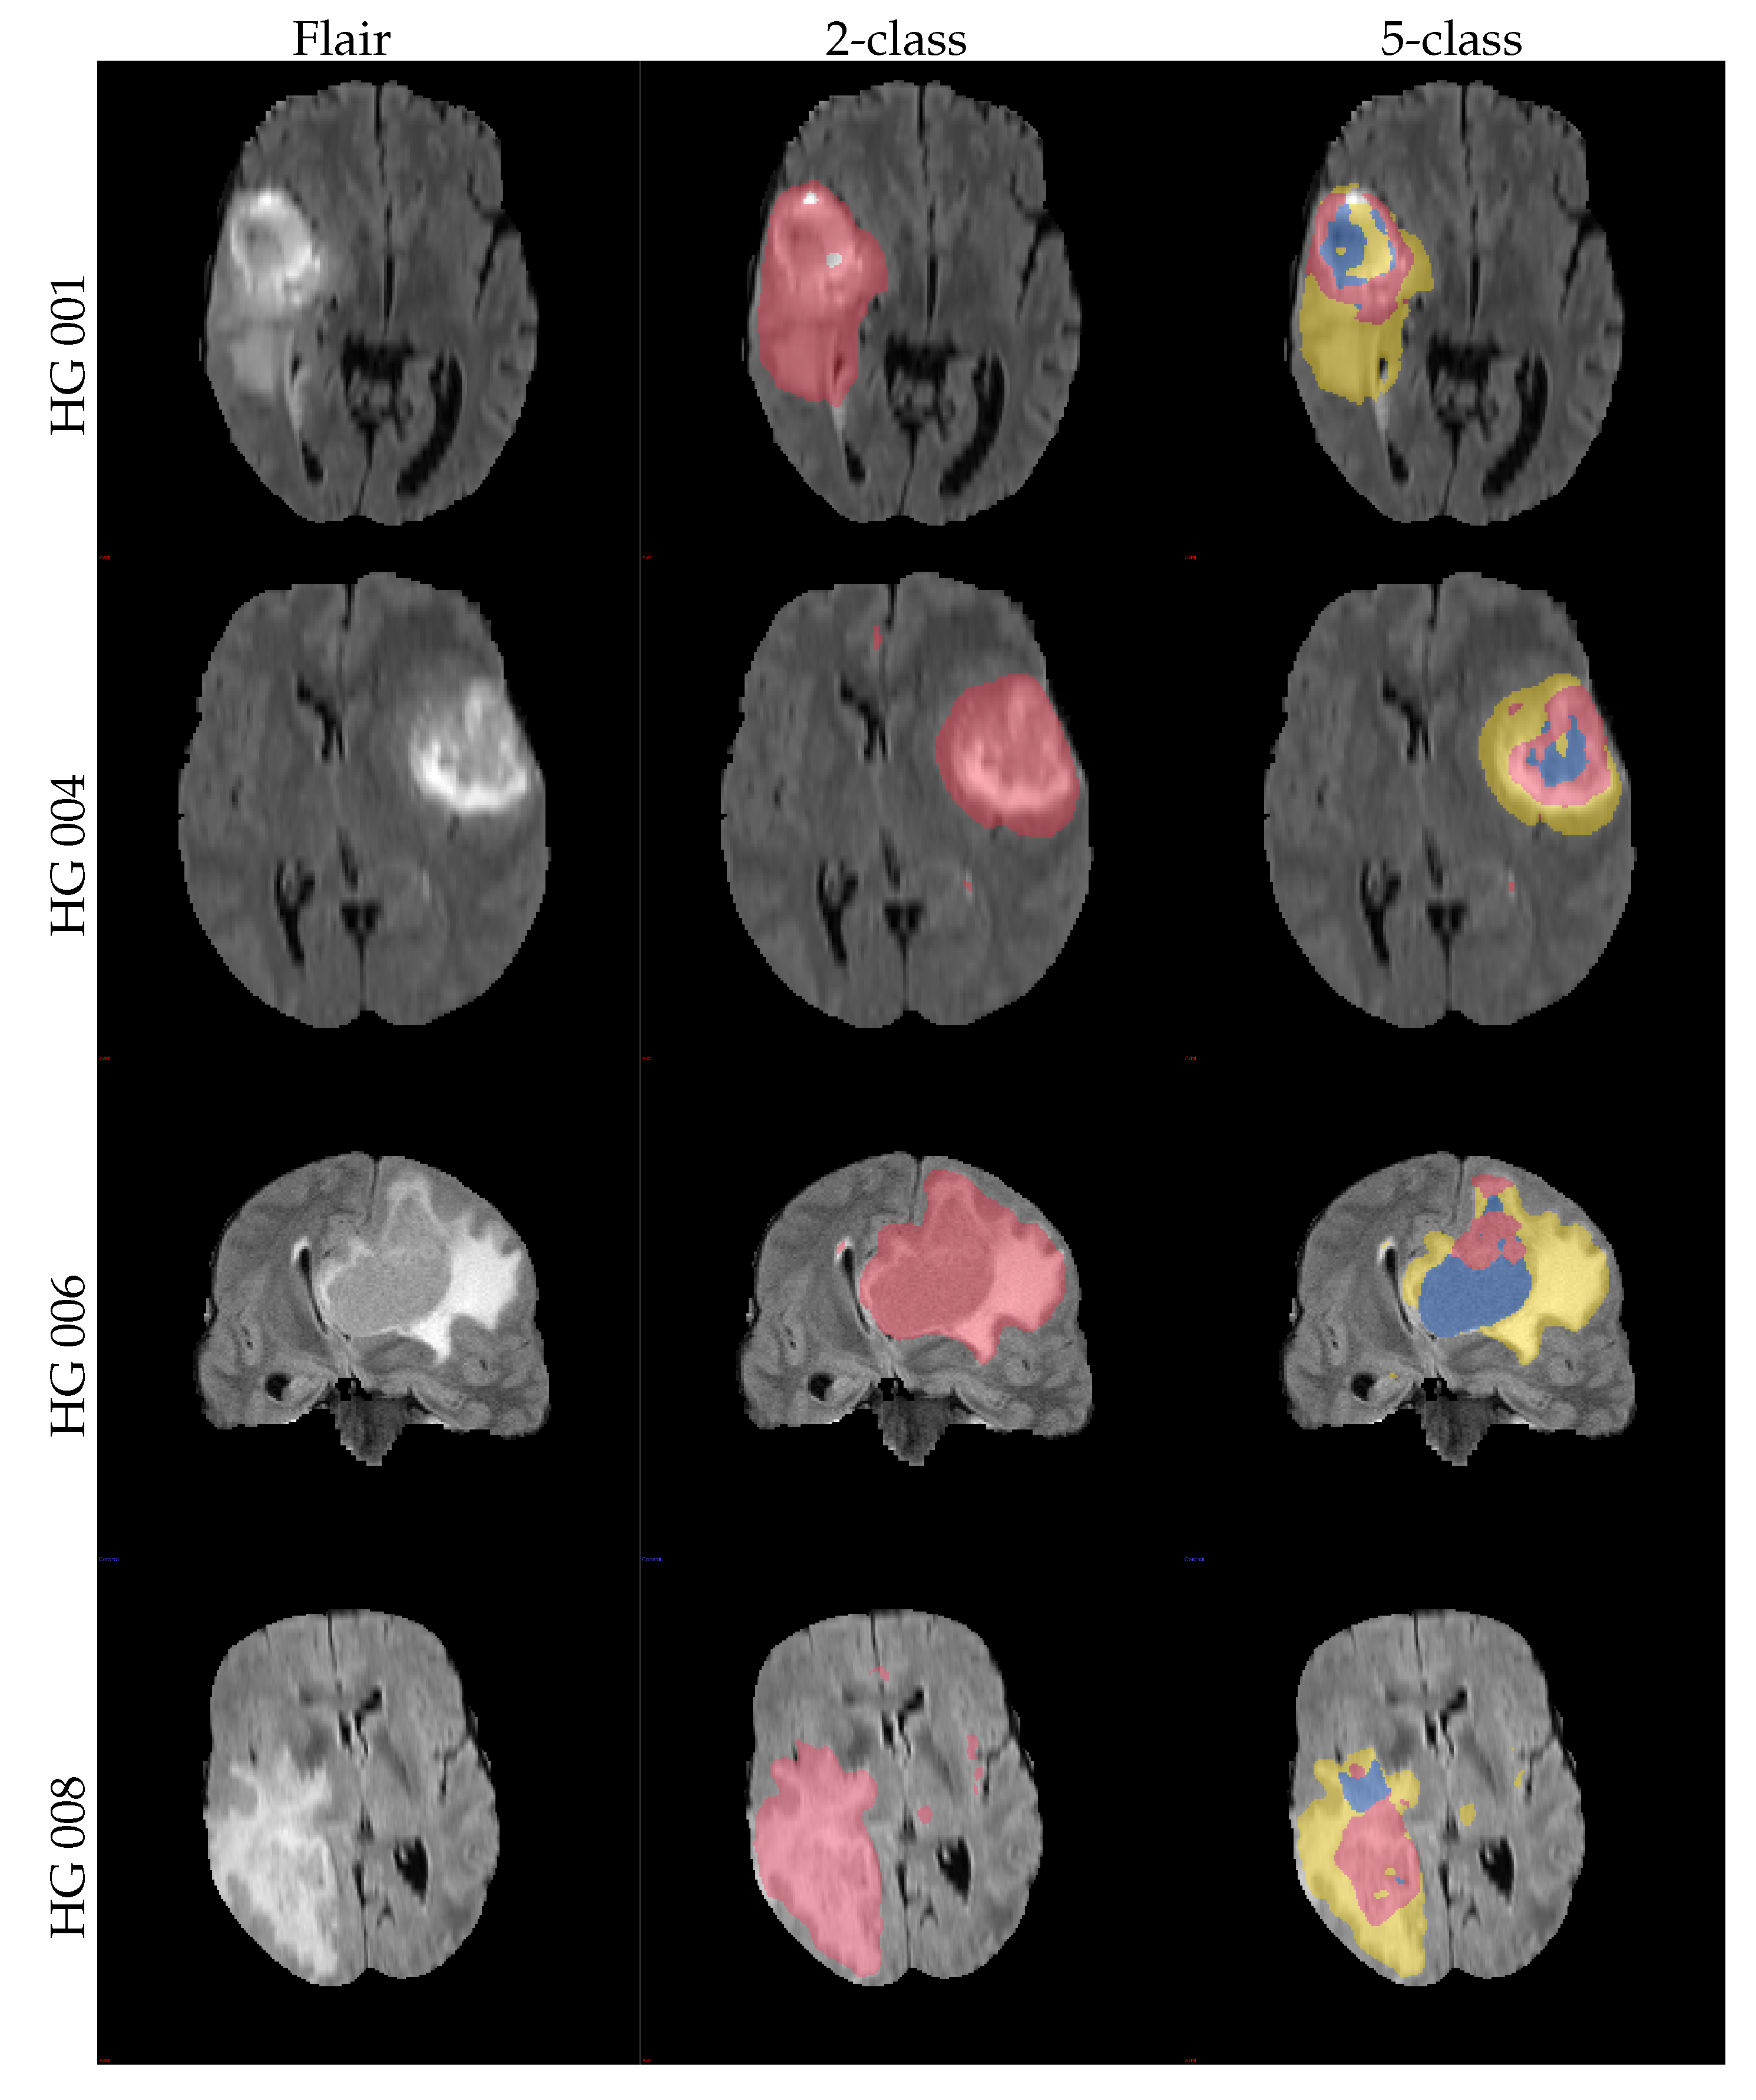

The obtained mean DICE score from leave-one-out experiments is 78.7% ± 15.7%, and the sensitivity and specificity are 78.3% ± 15.9% and 98.8% ± 1.2%, respectively. These results are inline with the expected results from other experiments and could be further improved using more sophisticated features and additional post-processing [17]. Figure 7 shows some examples of the obtained segmentation, both as two and multiclass results.

Figure 7.

Example axial and coronal (HG 006) slices from the validation set u(BraTS 2013 dataset) using the proposed PU-learning method. The colour coding is as follows: ‘yellow’: edema; ‘red’: enhancing tumour; ‘green’: non-enhancing tumour; ‘blue’: necrosis. The subject name is identical to the identifier within the original training dataset.